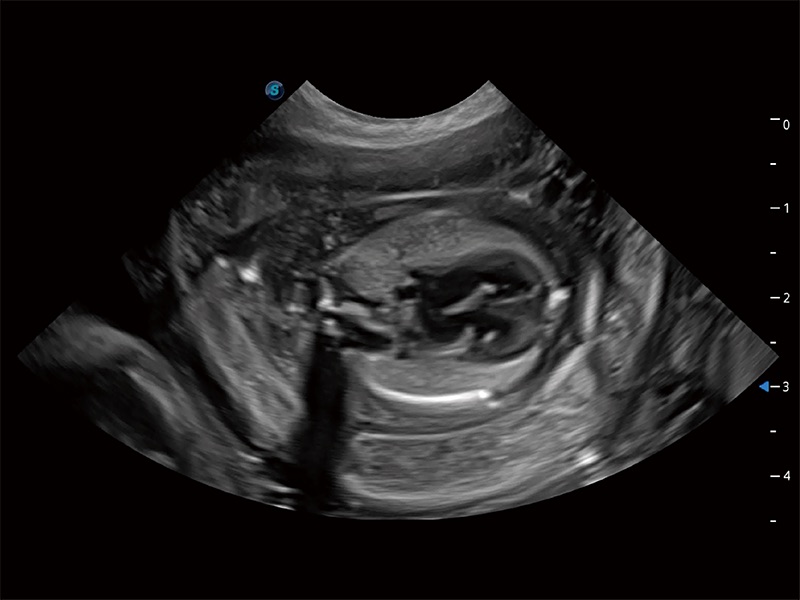

ProPet 80 专为动物医生设计,对不同的动物体型和生理结构作出了针对性的优化。通过动物影像专用软件,可满足个性化的应用需求,帮助动物医生获得更精确的诊断数据。

为精细结构及组织边缘提供高清晰度的图像和更大的成像视野。帮助减轻医生的用眼疲劳,快速精准获得测量的数据。

提供解剖示意图、标准超声图像、扫查手法涂和操作者实时检查图像,指导操作者进行标准切面的正确扫查。

针对宠物、马科、农场动物、实验室动物和异宠等20多种动物种类,预置丰富的动物注释及动物体标库。